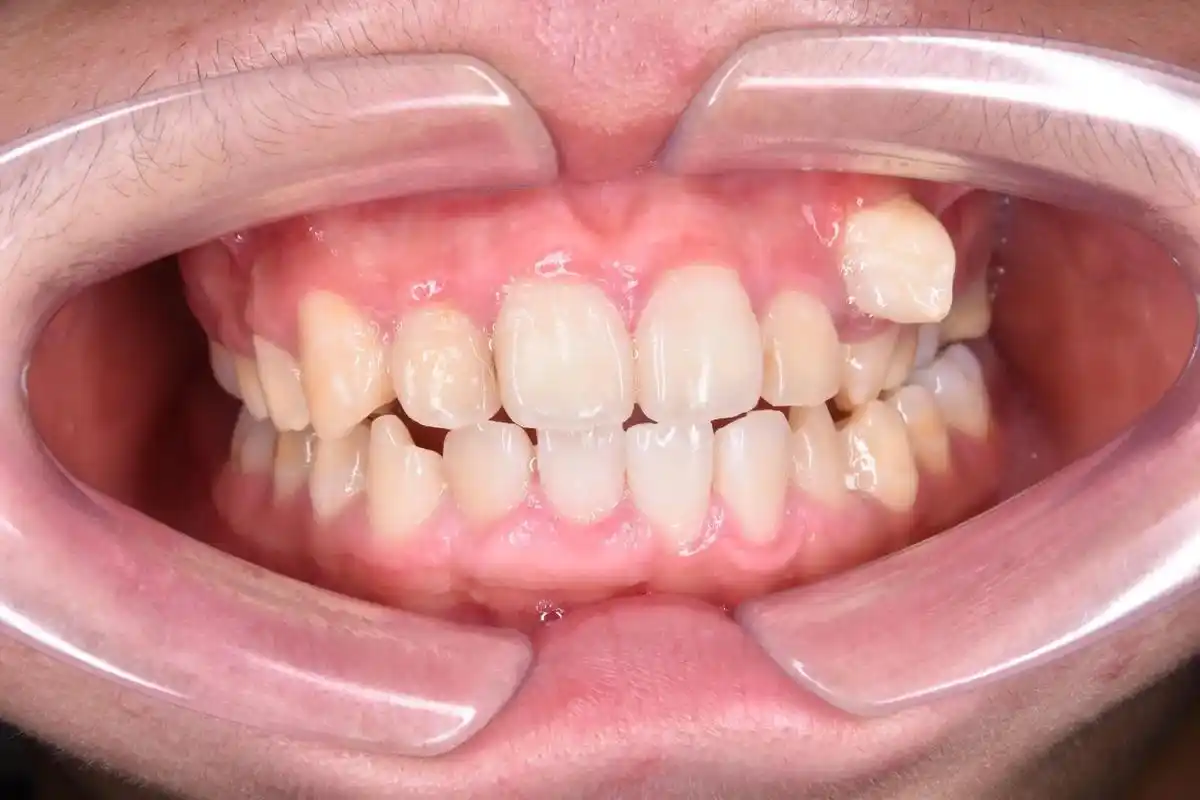

尖牙"虎牙"长歪了,经常有被误拔或被要求拔除,除非特殊情况, - 抖音

虎牙,也叫犬齿,是上颌处于门牙和臼齿之间的两颗单尖牙,同时,虎牙也是

又称犬齿,是一种常见的畸形牙,指唇侧错位的尖牙(上颌的两颗单尖牙)

恒尖牙一般是最晚长出来的,假如这颗牙齿的方位被其他牙齿所占据,就会